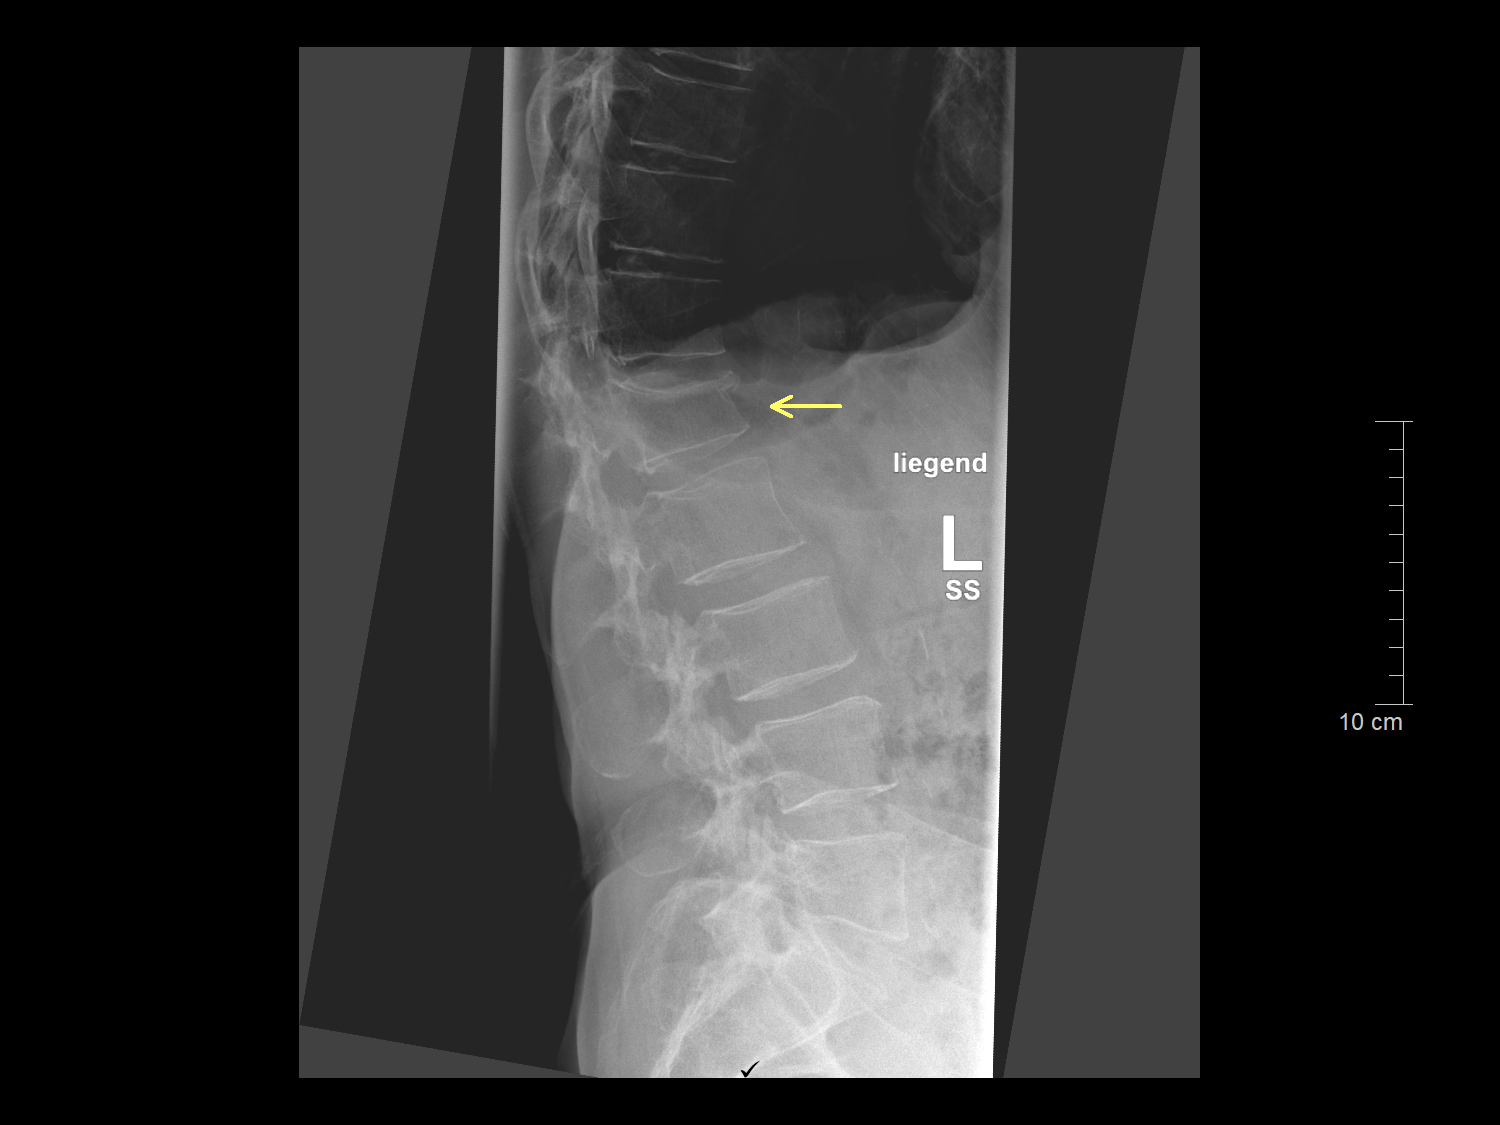

Röntgenuntersuchungen werden für eine Vielzahl von Zwecken eingesetzt, darunter die Diagnose von Knochenbrüchen, die Beurteilung von Organen wie Lunge, Herz und Verdauungstrakt sowie die Untersuchung von Weichteilgewebe auf Anzeichen von Verletzungen oder Erkrankungen. Die Röntgenbildgebung ist schnell, schmerzlos und nicht-invasiv und ermöglicht uns eine schnelle Diagnose und Behandlungsplanung.

Jedoch muss der Nutzen, der sich für den Patienten aus der Röntgendiagnostik ergibt, gegenüber dem der Strahlenexposition abgewogen werden. Das ist der Fall, wenn mit dieser Untersuchungsmethode die diagnostische Fragestellung beantwortet werden kann und kein alternatives Verfahren zu Verfügung steht. Zum Beispiel ist zu sicheren Diagnose und Therapieplanung eines Knochenbruches eine Röntgenaufnahme notwendig. Nach einer Operation sind Röntgenaufnahmen zur Material- und Lagekontrolle erforderlich.